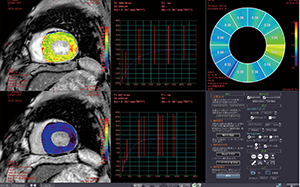

MRIは、心臓と頭部を中心に1日5件前後が行われている。Ziostation2では、非造影の冠動脈MRAの解析などを行っていたが、MRIで心臓のT1値の計測が可能になったことから、「MR心筋T1マッピング」を用いて心筋組織細胞外液分画(ECV)を心臓MRIの全例で計測している。MR心筋T1マッピングでは、造影前後のT1マッピングから血液のT1値とヘマトクリット値を利用してECVの定量評価ができる。粟木副部長は、「導入前は計測には準備や手間がかかるのではと構えていましたが、実際には従来のシーケンスを大きく変えずに追加でき、ROIの設定も簡単で計算も速いので、スループット良く運用できています」と説明する。MR心筋T1マッピングでは、「心筋の状態をカラー分布で表示してくれるので、全体を直感的に把握しやすく、臨床医にわかりやすい情報を提供できま

す。T1値の変化は、遅延造影(LGE)に描出されていなくても、心筋に何らかの変性が始まっていることが考えられ、予後の予測が可能になることが期待されます」(粟木副部長)と評価する。

図3 MR心筋T1マッピング |